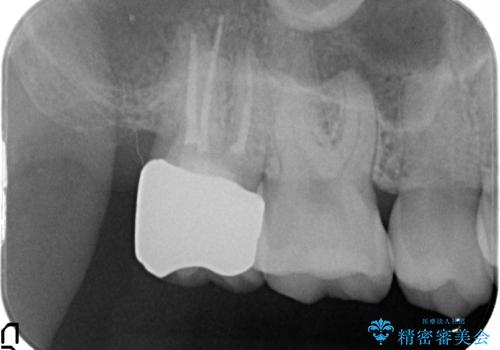

- 右上7の虫歯が大きく、他院にて抜歯と言われたが、なんとか残せないかと当院にいらっしゃった方の症例です。

自発痛の既往および持続痛を認めたため、カリエス除去後根管治療を行いました。

その後オールセラミッククラウンによる補綴を行いました。

今回用いたオールセラミッククラウンはジルコニアフレームという白い素材の上にセラミックを盛っているため、審美性が非常に高いのが特徴です。

また、ジルコニアは人工ダイヤモンドの材料にも使われているほど高い強度を持っており、そのためオールセラミッククラウンは審美性だけでなく、奥歯やブリッジの補綴も可能とするクラウンです。